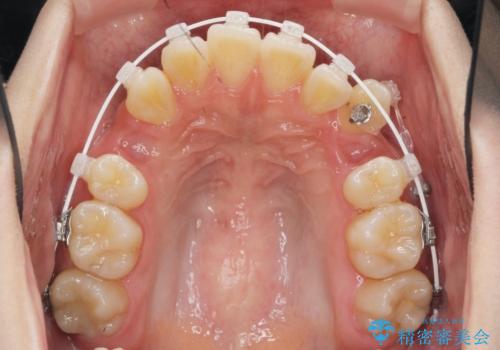

八重歯を矯正治療で治したい!

- 八重歯・がたつきのある歯並びの改善を求めて来院されました。

全部の歯が入り切るスペースがなかったため、小臼歯4本を抜去しワイヤーを用いたマルチブラケット矯正を選択しました。

歯並びの改善と共に、歯ブラシがしやすくなった!と喜んでいただくことができました。